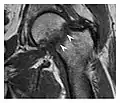

The greater tuberosity of the humerus is also an illustrative location of occult fractures. The osseous injury may follow seizures, glenohumeral dislocation, forced abduction, or direct impaction. They are commonly discovered on MRI in symptomatic patients with suspicion of rotator cuff tear. Coronal images are best suited for detection. They appear as crescentic oblique lines surrounded by a bone marrow edema pattern (Figure 5). The rotator cuff must be inspected since associated ligamentous lesions are common. In the ankle, malleoli and tarsal bones should be checked carefully for any cortical disruptions and radiolucent lines that may reveal a fracture. Awareness of the exact location of the pain will help direct the attention of the interpreter when searching for very subtle signs of fracture (Figure 6).[1]

a a

b b